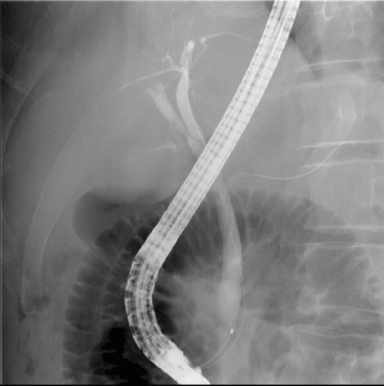

エックス線透視検査とは、バリウムと呼ばれる造影剤を使用した胃や大腸の検査のほか、手術後の透視、骨折や脱臼の整復、エックス線で透視した画像を見ながら内視鏡を用いて行うERCP(内視鏡的逆行性胆管膵管造影)、気管支鏡で組織を採取するTBLB(経気管支肺生検)などがあります。

内視鏡的逆行性胆管膵管造影